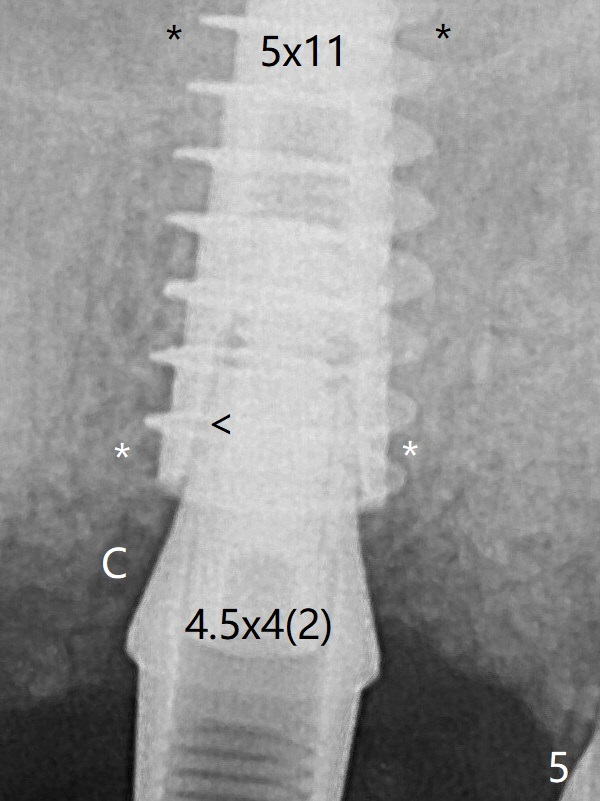

After use of 6 mm profile drill, a 4.5x4(3 (longer cuff)) mm abutment is able to be seated apparently completely without a gap (Fig.6).  The third round of bone graft (Fig.6 *) is placed around the abutment to make sure that the underlying implant is fully covered to reduce periimplantitis in the future.